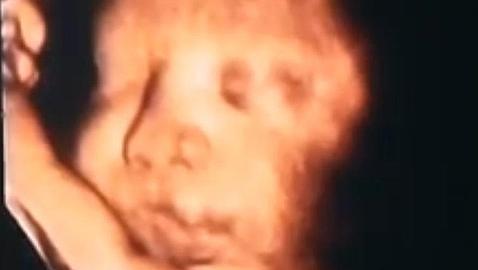

Hace sólo unos años hubiera tenido que esperar a dar a la luz para ver la carita de Daniel, su bebé, pero hoy, gracias a una ecografía 4D (así es como denominan a las 3D en movimiento), ha podido descubrir que el pequeño tiene sus gruesos labios y su nariz y que cuenta con «todos los deditos». Lo único que no se aprecia todavía, porque están cerrados, son los ojos, pero «algo de misterio tendrá que quedar para el día del nacimiento», responde sonriendo la futura mamá. Su papá, Diego, espera que herede los suyos, que son claros y algo rasgados, muy bonitos.

No sabemos cómo será el carácter del pequeño, aunque con un padre brasileño, una madre venezolana y una abuela española, seguro que genio no le va a faltar. En su primera aparición en los medios parece tranquilo, como si estuviera posando, se ha dejado ver y nos ha regalado algunas poses, un bostezo y algún pucherito. Duerme plácido, calentito y ajeno a lo que le espera ahí fuera.

Daniel viene grandecito. Ya es un bebé de dos kilos y medio y todavía le quedan cinco semanas para seguir creciendo dentro de su madre. «A través de la ecografía, teniendo en cuenta tres parámetros (longitud del fémur, diámetro biparental y la circunferencia abdominal) se puede determinar el peso», nos explica Diana Flores, ecógrafa de la Clínica Eres, que se esmera por captar las mejores imágenes del pequeño.

«Es una técnica no invasiva, no existen contraindicaciones ni para la madre ni para el niño», recuerda Flores, que advierte que el mejor momento para someterse a este tipo de ecografía es entre la semana 25 y 30 del embarazo «porque es cuando mejor se aprecia». Con Daniel hemos tenido suerte porque aunque su madre está ya de casi 35 semanas se ha dejado ver perfectamente.